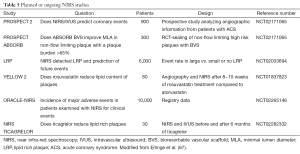

The common outcomes reported in the coronary atherosclerosis are summarized in Tables 1 and 2, which illustrate significant heterogeneity in the definition of outcomes, not only the variety in definitions of MACE but the inclusion or exclusion of all-cause mortality and unstable angina in various trials. There is also further fragmentation of definitions with some trials including only angina requiring hospitalization vs. requiring intervention vs. all angina. Clearly the presence of “stenosis >50%” on angiography does not carry the same weight as “cardiac death”. Given predictive value of a test is clearly influenced by the outcome measured it should serve as a caution pertaining to the subsequent discussion and indeed in any assessment of outcome measures.

The follow-up duration in a clinical study closely parallels the era when a modality becomes available for widespread-use. Table 1 clearly illustrates how CAC/CA score, CTCA, Plaque assessment and cMRA all have progressively lower/shorter durations of follow-up. As such any differences in event rates need to be interpreted in light of this follow-up period. From an invasive perspective, this difference is mirrored in the paucity of predictive supporting OCT compared to IVUS (Table 2).